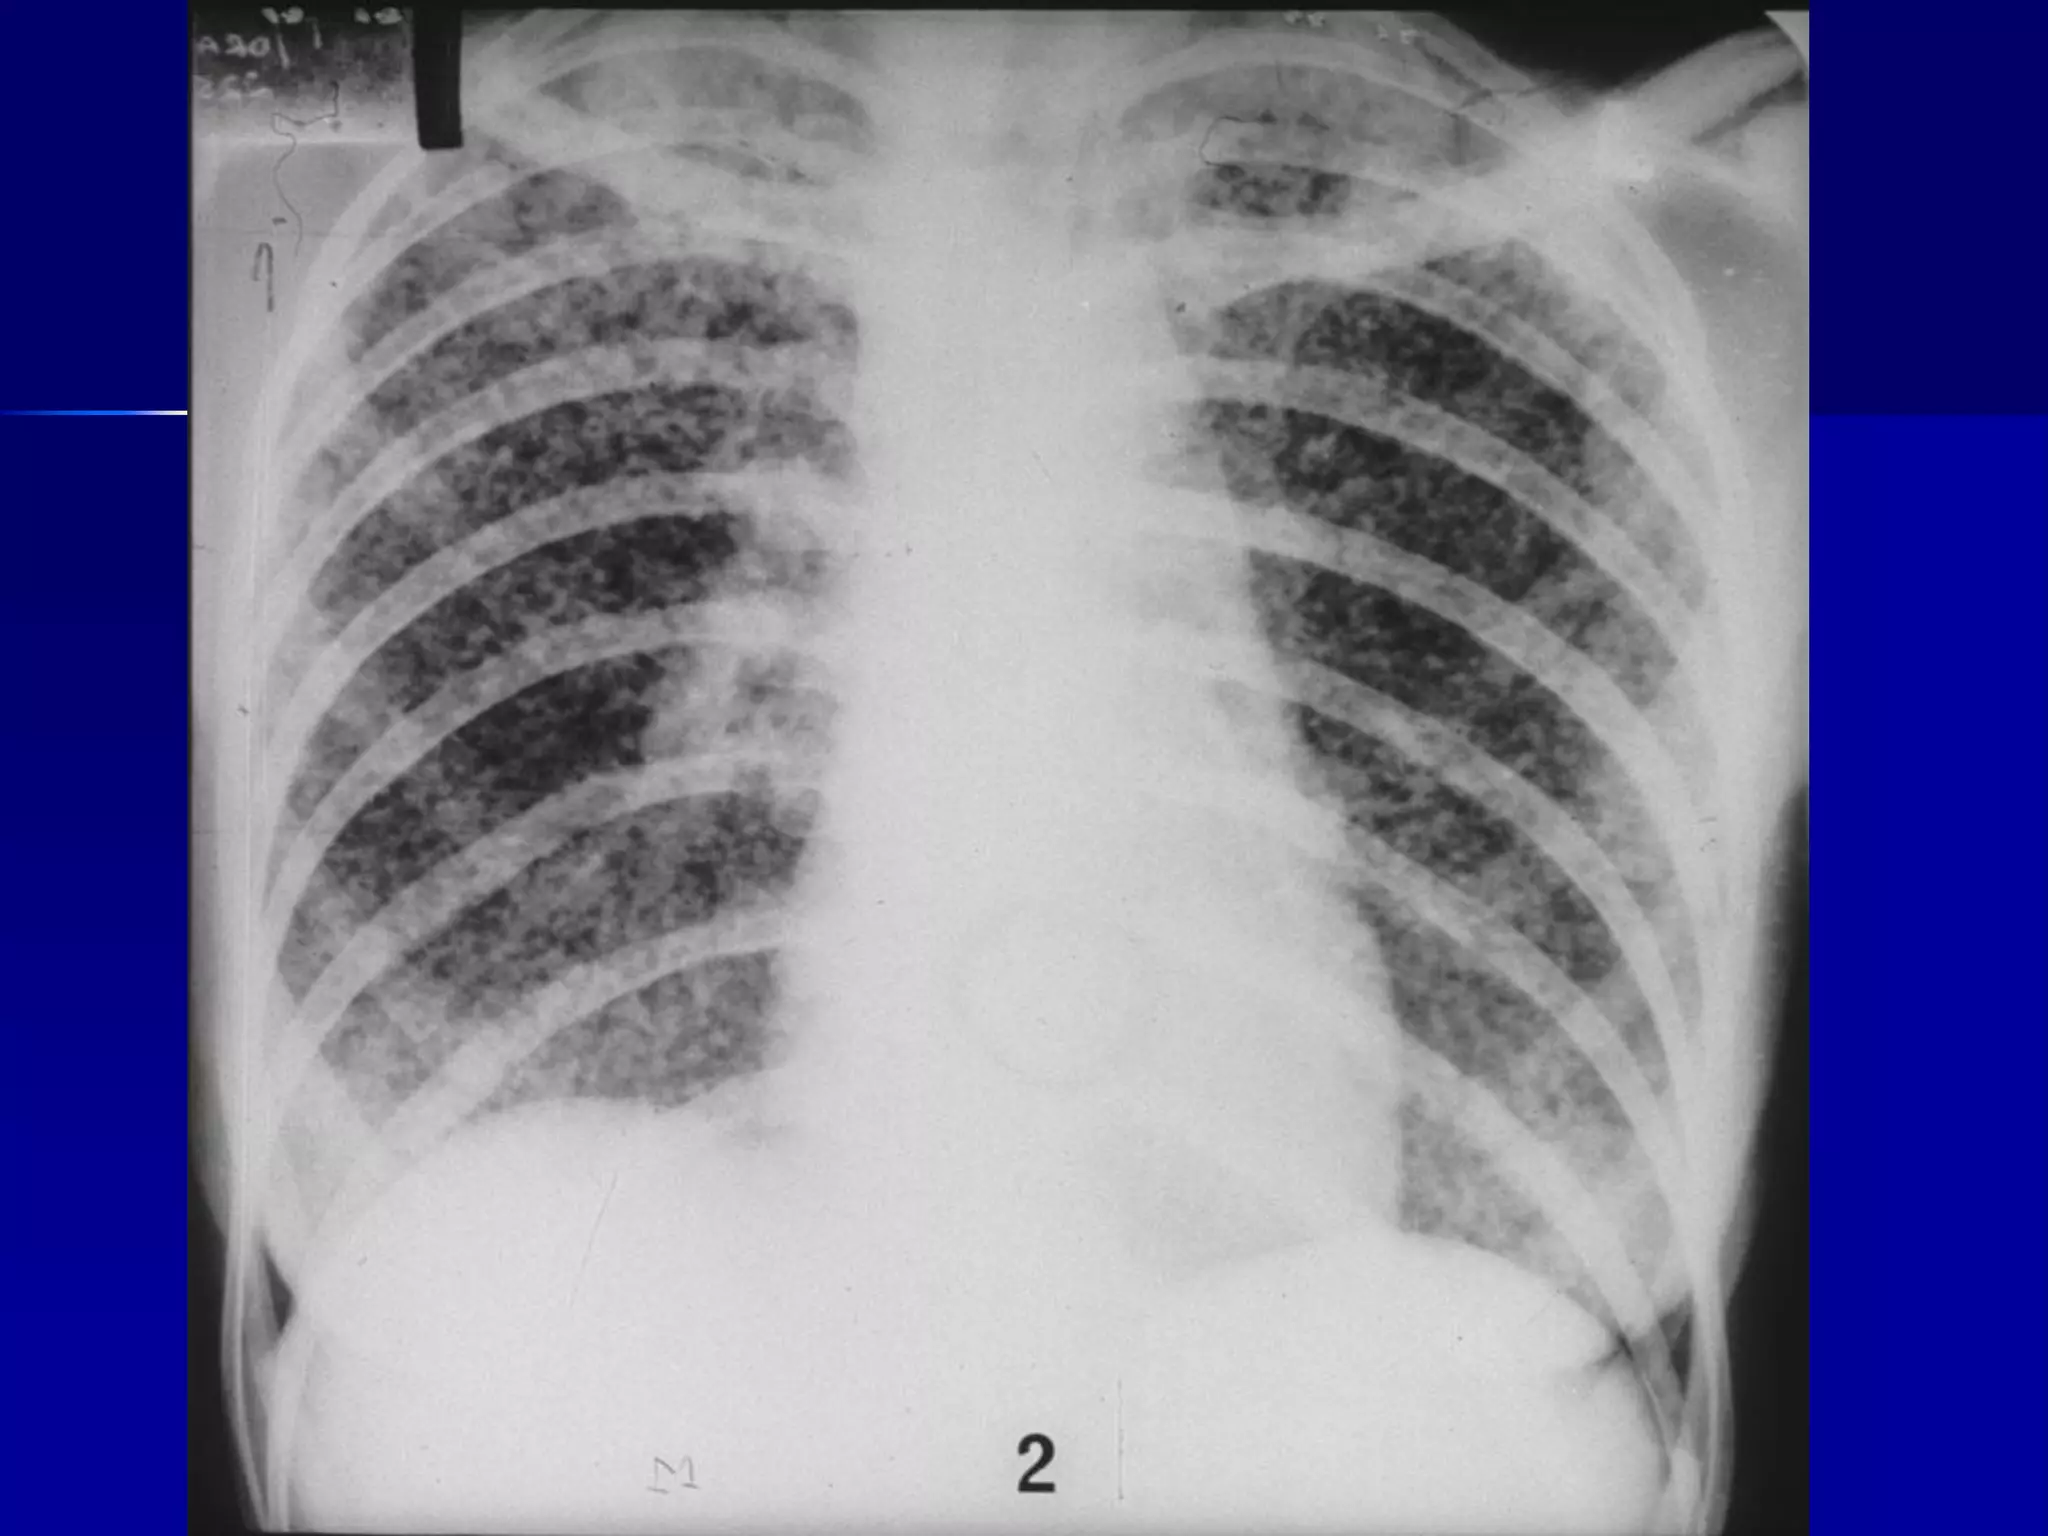

Miliary Tuberculosis

Produced by acute dissemination of tubercle

bacilli via the blood stream.The term miliary

derives from the radiological picture of

diffuse, discrete nodular shadows about the

size of millet seed (2mm).

A- Classical form:

Clinical features:

Most common in infants and young children with acute

or subacute febrile illness.

In adults: the onset is insidious, gradual vague ill health.

Malaise, Cough (usually dry), dyspnea. Night sweat is

less common.

Headache suggest associated tuberculous meningitis

Chest examination is free, crepitations may be found.

Hepatomegaly, splenomegaly, lymphadenopathy,

neck rigidity may be found in rare cases.

Miliary TB

􀂄 Earliest form of miliary TB is detectable

on HRCT.

􀂄 Coalescing nodules result into patchy

irregular

opacities and HRCT shows this variation

effectively

and has been described as “snowstorm

appearance”.

􀂄 HRCT shows cavitation, which is not

evident on plain

CXR.